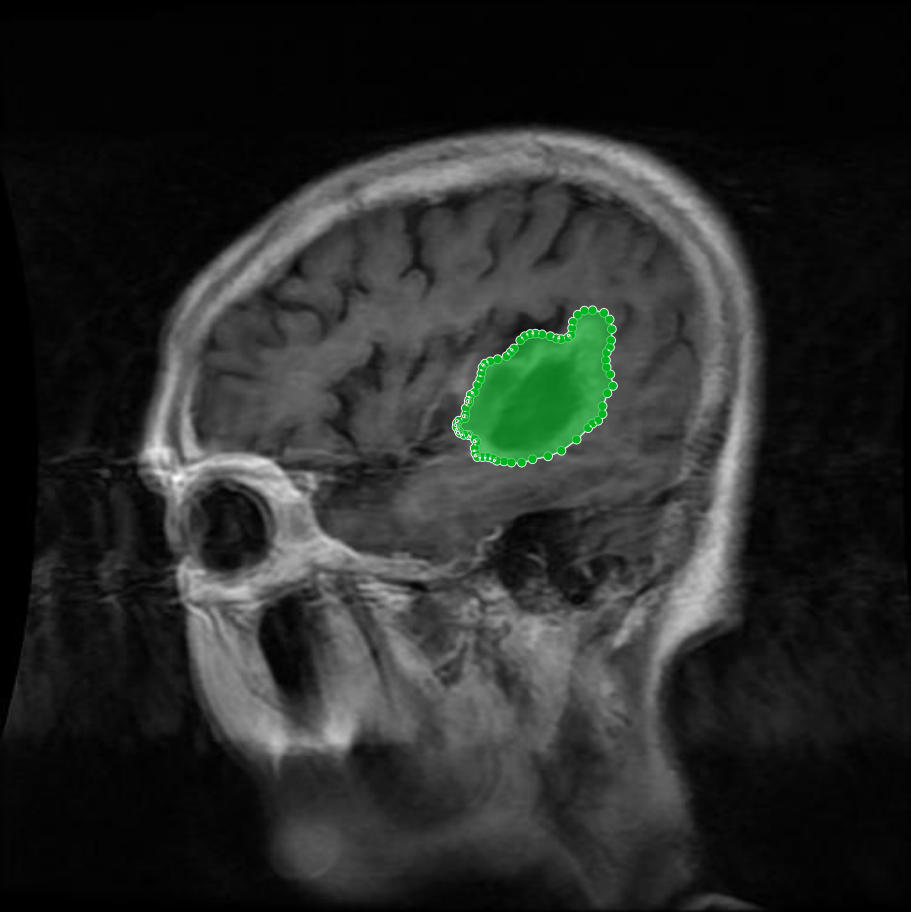

Meningioma: Meningiomas arise from the meninges and are generally well‑circumscribed and homogeneous, making them easier to segment. However, their location adjacent to critical structures such as dural sinuses and cranial nerves can complicate diagnostic tasks. An example of a meningioma and its segmentation mask is presented in Figure 2, illustrating the clarity of its boundaries.

Figure 2: Samples of Meningioma segmentation across different imaging planes

The dataset encompasses four distinct classes: ”Glioma”, ”Meningioma”, ”Pituitary” tumors, and ”non-tumorous”. As detailed in Section Overview of Brain Tumors, each class presents unique characteristics and complexities. This subsection offers representative visual examples from each class, including raw MRI scans alongside their annotated tumor masks, emphasizing the diversity and precision of the dataset. Glioma: Gliomas are irregularly shaped and often infiltrate surrounding tissues, presenting significant challenges for precise boundary definition. These complexities require robust segmentation techniques to capture their variable morphology. As shown in Figure 1, gliomas exhibit irregular and diffuse growth patterns, which are highlighted through annotated tumor masks. Meningioma: Meningiomas arise from the meninges and are generally well‑circumscribed and homogeneous, making them easier to segment. However, their location adjacent to critical structures such as dural sinuses and cranial nerves can complicate diagnostic tasks. An example of a meningioma and its segmentation mask is presented in Figure 2, illustrating the clarity of its boundaries. Pituitary Tumors: Located at the base of the brain near critical structures like the optic chiasm, pituitary tumors demand careful delineation to avoid diagnostic errors. As shown in Figure 3, the segmentation accurately captures the tumor’s boundaries without encroaching on adjacent critical regions. Non-tumorous: This control class includes both healthy brain scans without visible abnormalities and scans with non-neoplastic, space-occupying lesions (e.g., cysts, abscesses, or vascular malformations). Incorporating such cases improves the dataset’s robustness for both binary (tumorous vs. non-tumorous) and multi-class classification tasks. Figure 4 presents representative examples of healthy and non-tumorous lesion cases across different imaging planes.Tumor Mask and Annotation Quality